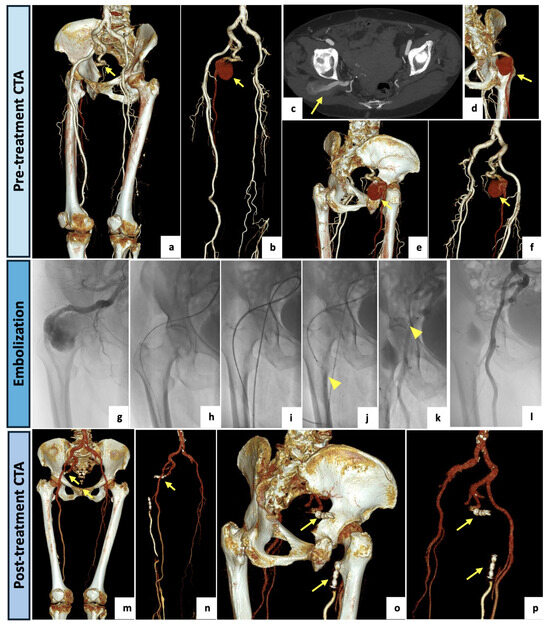

Figure 5.

(a–e) Intraprocedural selective angiographic images obtained after a left antegrade common femoral access. (a–e) The angiograms demonstrate a diffusely hypoplasic and interrupted left SFA, lacking the usual continuation, and a popliteal artery supplied by collateral pathways originating from the distal small branches of the SFA and the deep femoral axis. (b,c) Surprisingly, an arterial vessel suggestive of incomplete PSA was retrograde perfused via deep femoral collateral pathways and visualized both proximally and distally as brief tracts (yellow arrows). (f–i) Axial and coronal maximal intensity projection views of the CTA confirming a bilateral PSA. On the left side, a type 2A PSA (yellow arrows) and a distal significant stenosis of the SFA (yellow asterisk) were detected. The right lower limb presented a type 1 complete PSA (orange arrow) along with a regular SFA (orange asterisk). (j–m) Three-dimensional reconstructions with and without bone structures. On the left side, a type 2a PSA with a proximal focal occlusion and re-habitation via gluteal collateral pathways, and a distal femoral significant stenosis was detected (yellow arrows). The right lower limb presented a type 1 complete PSA (orange arrows).